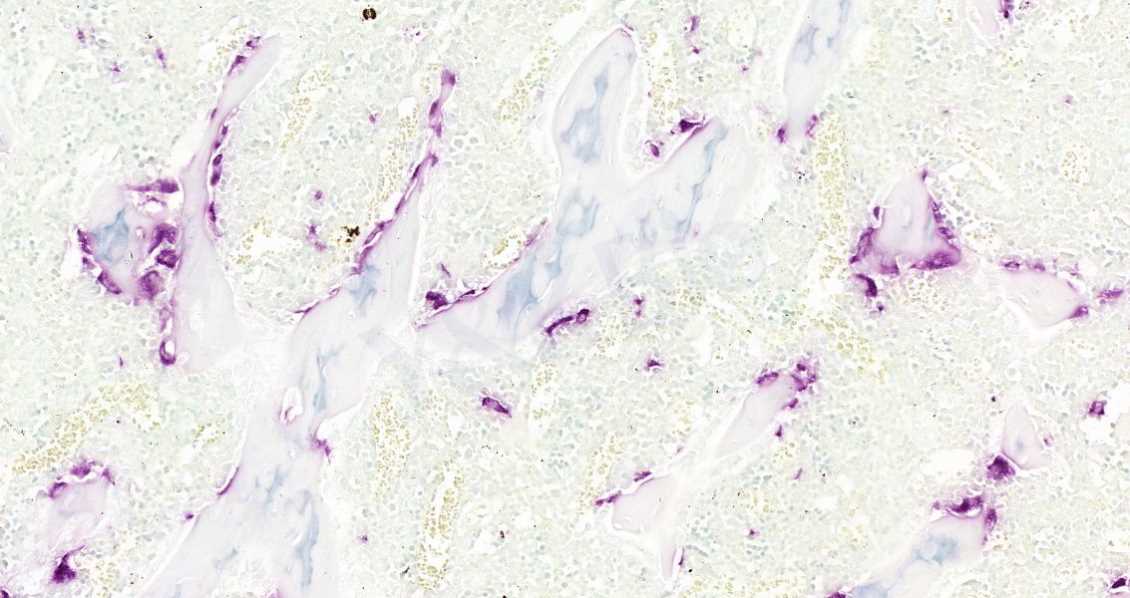

4.Trap染色

Trap染色是用于检测骨组织、骨细胞中特征物质的染色,使破骨细胞呈红色,背景呈绿色或蓝色。抗酒石酸酸性磷酸酶(Trap)为破骨细胞的标志酶,特异地分布于破骨细胞中,为破骨细胞所特有,通常作为鉴别破骨细胞的重要标志物。

软骨基质对甲苯胺蓝的异染性,是因为软骨基质的主要成分是软骨黏蛋白、多糖物质,而酸性硫酸根与嗜碱性染料有亲和力。此法用于显示新生骨组织钙盐沉积,成骨细胞数目统计,观察软骨退变,软骨细胞坏死钙化,软骨基质裂隙,胶原纤维增生等病理改变。染色结果:软骨和成骨细胞呈蓝紫色,背景呈淡蓝色。